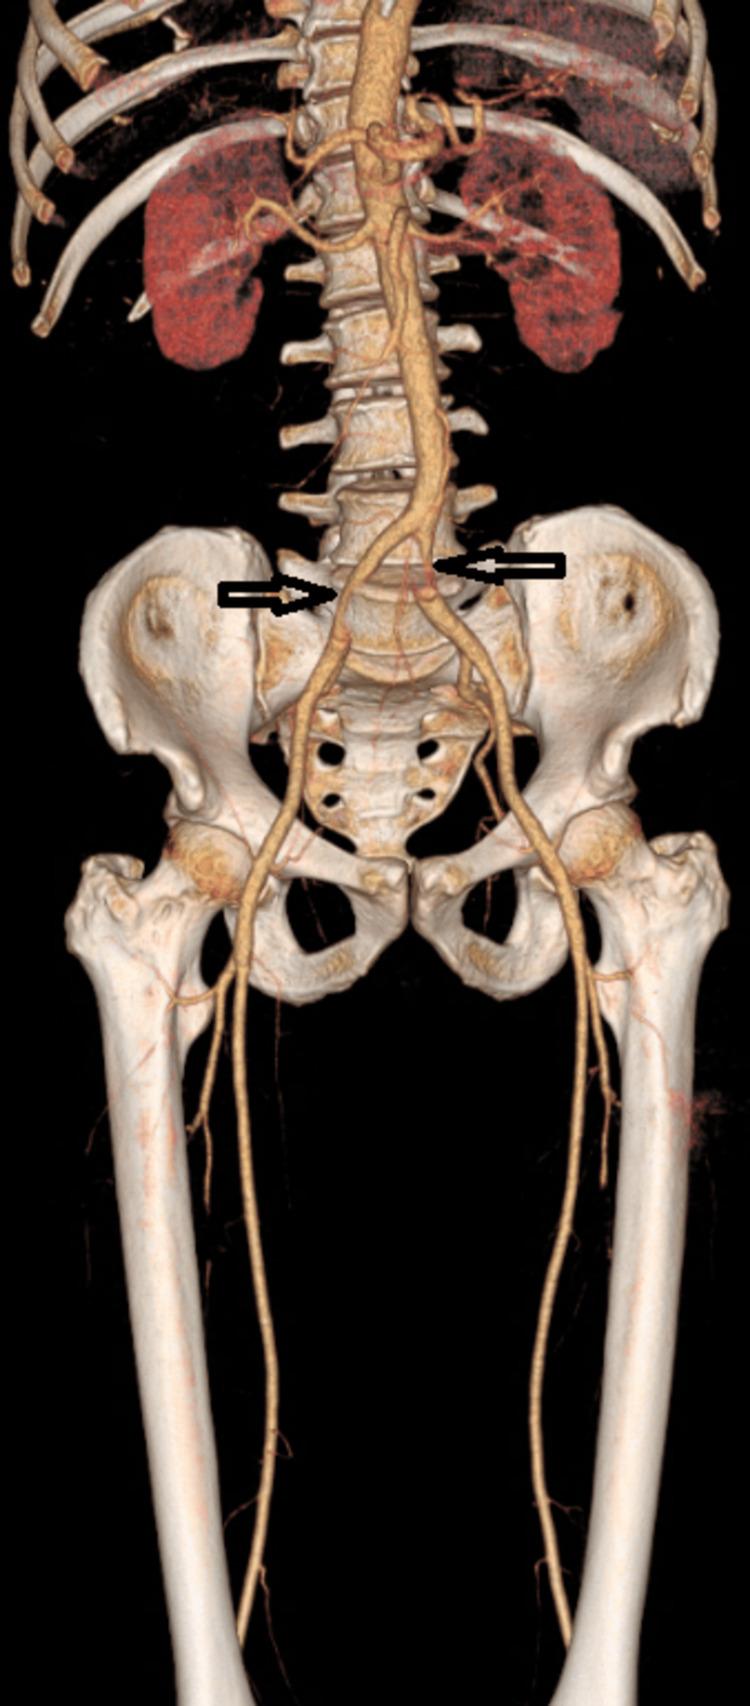

Introduction Severe acute respiratory syndrome coronavirus 2 (SARS-CoV-2) infection is currently known to lead to high rates of thrombotic complications. Of those, acute limb ischemia (ALI) was most frequently reported. Several case reports or case series had already described high mortality and amputation rates. The purpose of our study was to highlight the epidemiological, clinical, and management characteristics of coronavirus disease 2019 (COVID-19)-related ALI patients. Methods This was a monocentric, observational, and retrospective study. Records of all patients ≥18 years of age admitted with ALI and a confirmed diagnosis of COVID-19 infection between March 2020 and December 2021 were retrospectively examined. Data collected included demographics, co-morbidities, biological findings, COVID-19 pneumonia and ALI severity, anatomical location of arterial thromboembolism, treatments, and outcomes. Results During the study period, 22 patients with ALI infected with COVID-19 were evaluated. The median age was 67 years (45-88) and 18 (81.8%) were men. The main comorbidities were diabetes mellitus (36.4%), smoking (22.7%), and arterial hypertension (18.2%). All 22 patients were already diagnosed positive for SARS-CoV-2. The median duration between COVID-19 diagnosis and ALI symptom onset was six days (1-13 days). The computed tomography (CT) extent of pulmonary lesions was assessed according to the French Society of Chest Imaging. The ischemic syndrome was classified on Rutherford Stage IIA (30.4%) and IIB (43.5%). Regarding thrombotic locations, ALI had occurred essentially in the lower limbs (95% vs. 5%). A revascularization procedure was performed in 14 patients (63.6%) of the patients, and primary amputation was unavoidable in five patients (22.7%). Three patients (13.6%) did not undergo operative management, two because of their hemodynamic instability and one rejected surgery. We performed 23 revascularization procedures for 14 patients and three primary amputations. Thromboembolectomy (TE) was the technique of choice (92.8%). Below-the-knee (BTK) femoropopliteal bypass was performed in one patient. Selective tibial vessel thrombectomy was performed in four patients (28.6%). The mortality rate was 27.3%. Among survivors, two secondary amputations were needed with a limb salvage rate of 68.2%. Conclusion By the apparent end of the pandemic, our study further supports the increased risk of ALI in COVID-19-positive patients. Moreover, the results affirm the unfavorable outcomes highly impacted by rethrombosis, reinterventions, and consequently high rates of amputations and mortality.

结果 在研究期间,对22例感染COVID-19的ALI患者进行了评估。中位年龄为67岁(45 - 88岁),18例(81.8%)为男性。主要合并症为糖尿病(36.4%)、吸烟(22.7%)和动脉高血压(18.2%)。所有22例患者SARS-CoV-2检测均呈阳性。COVID-19诊断至ALI症状出现的中位时间为6天(1 - 13天)。根据法国胸部影像学会评估肺部病变的计算机断层扫描(CT)范围。缺血综合征根据卢瑟福分级为IIA期(30.4%)和IIB期(43.5%)。关于血栓形成部位,ALI主要发生在下肢(95%对5%)。14例患者(63.6%)接受了血运重建手术,5例患者(22.7%)不可避免地进行了一期截肢。3例患者(13.6%)未接受手术治疗,2例因血流动力学不稳定,1例拒绝手术。我们为14例患者进行了23次血运重建手术和3次一期截肢。血栓切除术(TE)是首选技术(92.8%)。1例患者进行了膝下股腘动脉旁路移植术。4例患者(28.6%)进行了选择性胫血管血栓切除术。死亡率为27.3%。在幸存者中,需要进行2次二期截肢,肢体挽救率为68.2%。